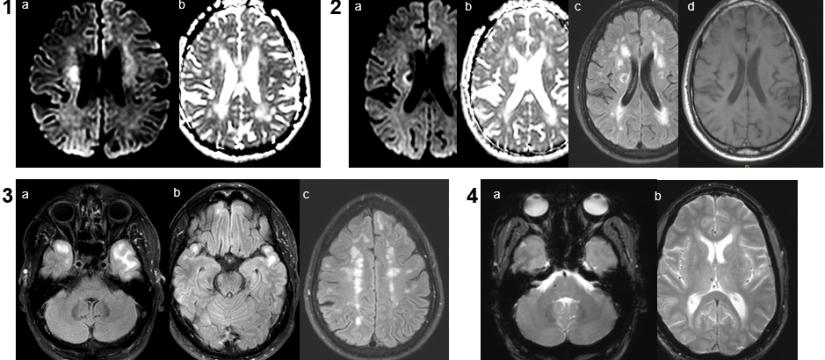

Mujer de 69 años de edad, con un cuadro de 7 meses de inestabilidad cefálica y de la marcha. Se realiza una RM craneal inicial, que es normal. Progresivamente, la síntomatología empeora, añadiéndose desorientación, alucinaciones, mioclonías y deterioro cognitivo. Se repite RM craneal por empeoramiento clínico progresivo.